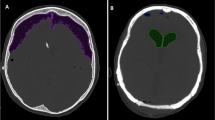

As shown in Fig. 2, the presence of right-sided hemoventricle detected at CT was clearly visible at TCS in patient 1. Similarly, the course of catheter was also visible at TCS (Fig. 3). Among the other qualitative parameters, the falx and the choroidal plexus, posterior cranial fossa, and brainstem were clearly visible in all patients (Fig. 4).

Intracranial evaluation before shunting (a, CT scan; b, transcranial ultrasound). Ventricular size and intracranial anatomy are clearly visible with transcranial ultrasound. In particular, the PEEK window allows us to also identify complications such as hemoventricle. clPT, contralateral parietal teca, CP, cranioplasty, CT, computed tomography, IVC, intraventricular catheter, lOH, left occipital horn, PEEK, polyetheretherketone, rFH, right frontal horn, SP, septum pellucidum